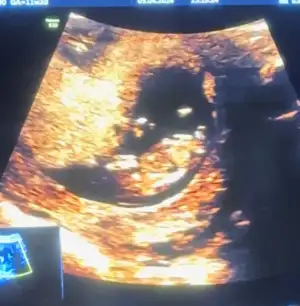

Nub teorisine göre cinsiyet tahmini yapabilen var mııı

Bizde 13 haftalık olduk bana da tahminde bulunabilir misiniz çok merak ediyorum 💕💕